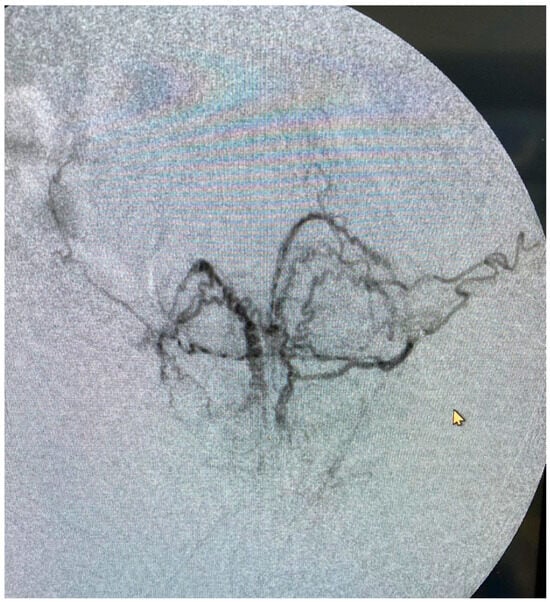

Figure 4.

Angiogram of the distal prostatic arteries demonstrating the size and intensity of the periurethral vasculature.